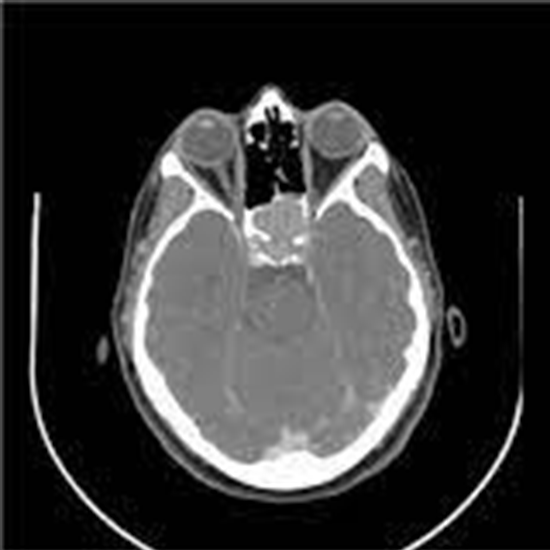

CT(Computed Tomography) Sella coronal Plain is an imaging technique that is used to create pictures of front and back views of pituitary sella. It is usually recommended to identify the problems affecting the pituitary gland.

CT Sella Coronal Plain is an imaging diagnostic tool that is used to look for the conditions of the front and back of pituitary sella and surrounding areas. Patients should not avoid any symptoms related to pituitary injuries, abnormalities or disorders. Patients should go for screening to avoid any delay in diagnosis and treatment of the pituitary sella.